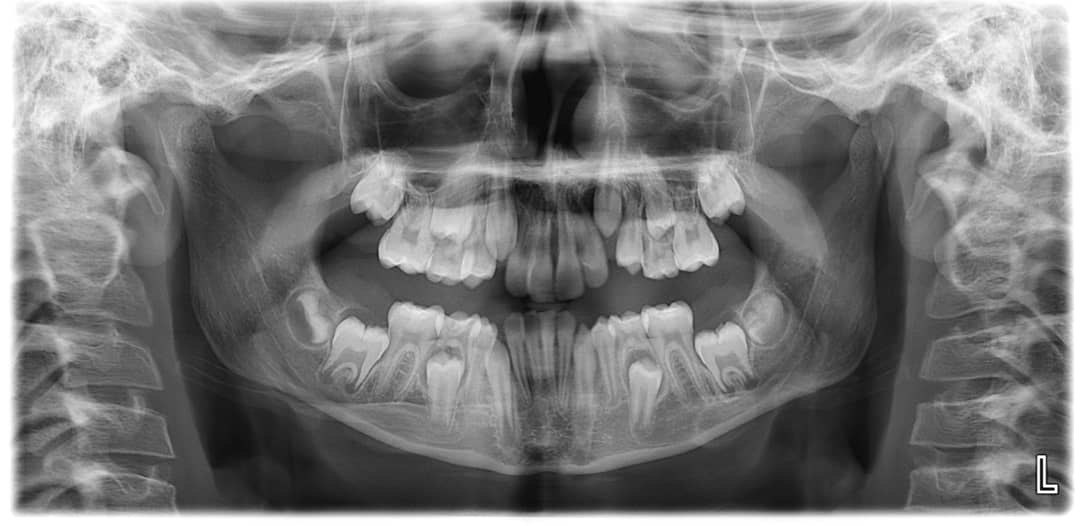

4. How old is the patient with the following X ray?